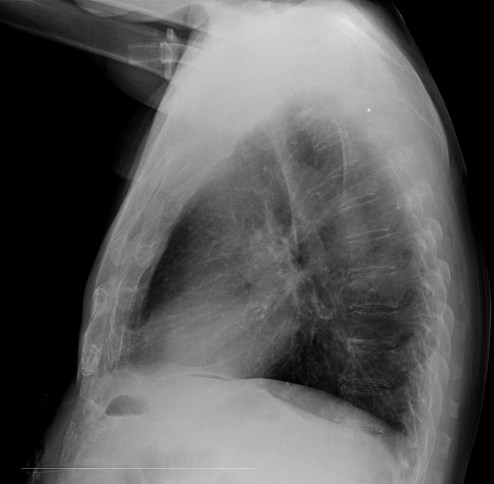

CASO: Febrícula y tos de 4 días de evolución.

Hallazgos:

- En la placa PA se observa una asimetría en los hilios pulmonares, el hilio izquierdo tiene una densidad aumentada.

- Tras examinar la placa lateral se observa un aumento de densidad en la columna que puede ser compatible con una condensación, es el signo de la desnificación vertebral.

SIGNO DE LA DENSIFICACIÓN VERTEBRAL: En la radiografía lateral normal, la densidad de la columna torácica tiende a disminuir desde la parte superior hasta el diafragma; la alteración de ese patrón por la presencia de una densidad superpuesta a la columna, indica la existencia de una consolidación pulmonar. Este signo adquiere especial valor cuando en la proyección posteroanterior la consolidación está oculta en el espacio retrocardíaco o en la base pulmonar.